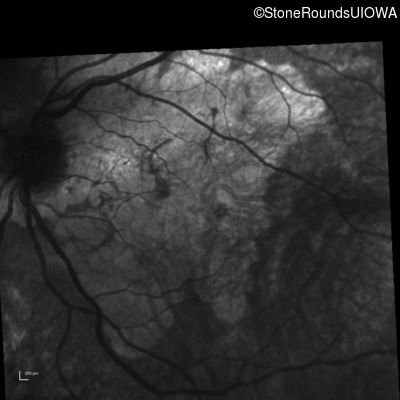

Infrared Fundus Photograph - Left - 20/200

Exemplar